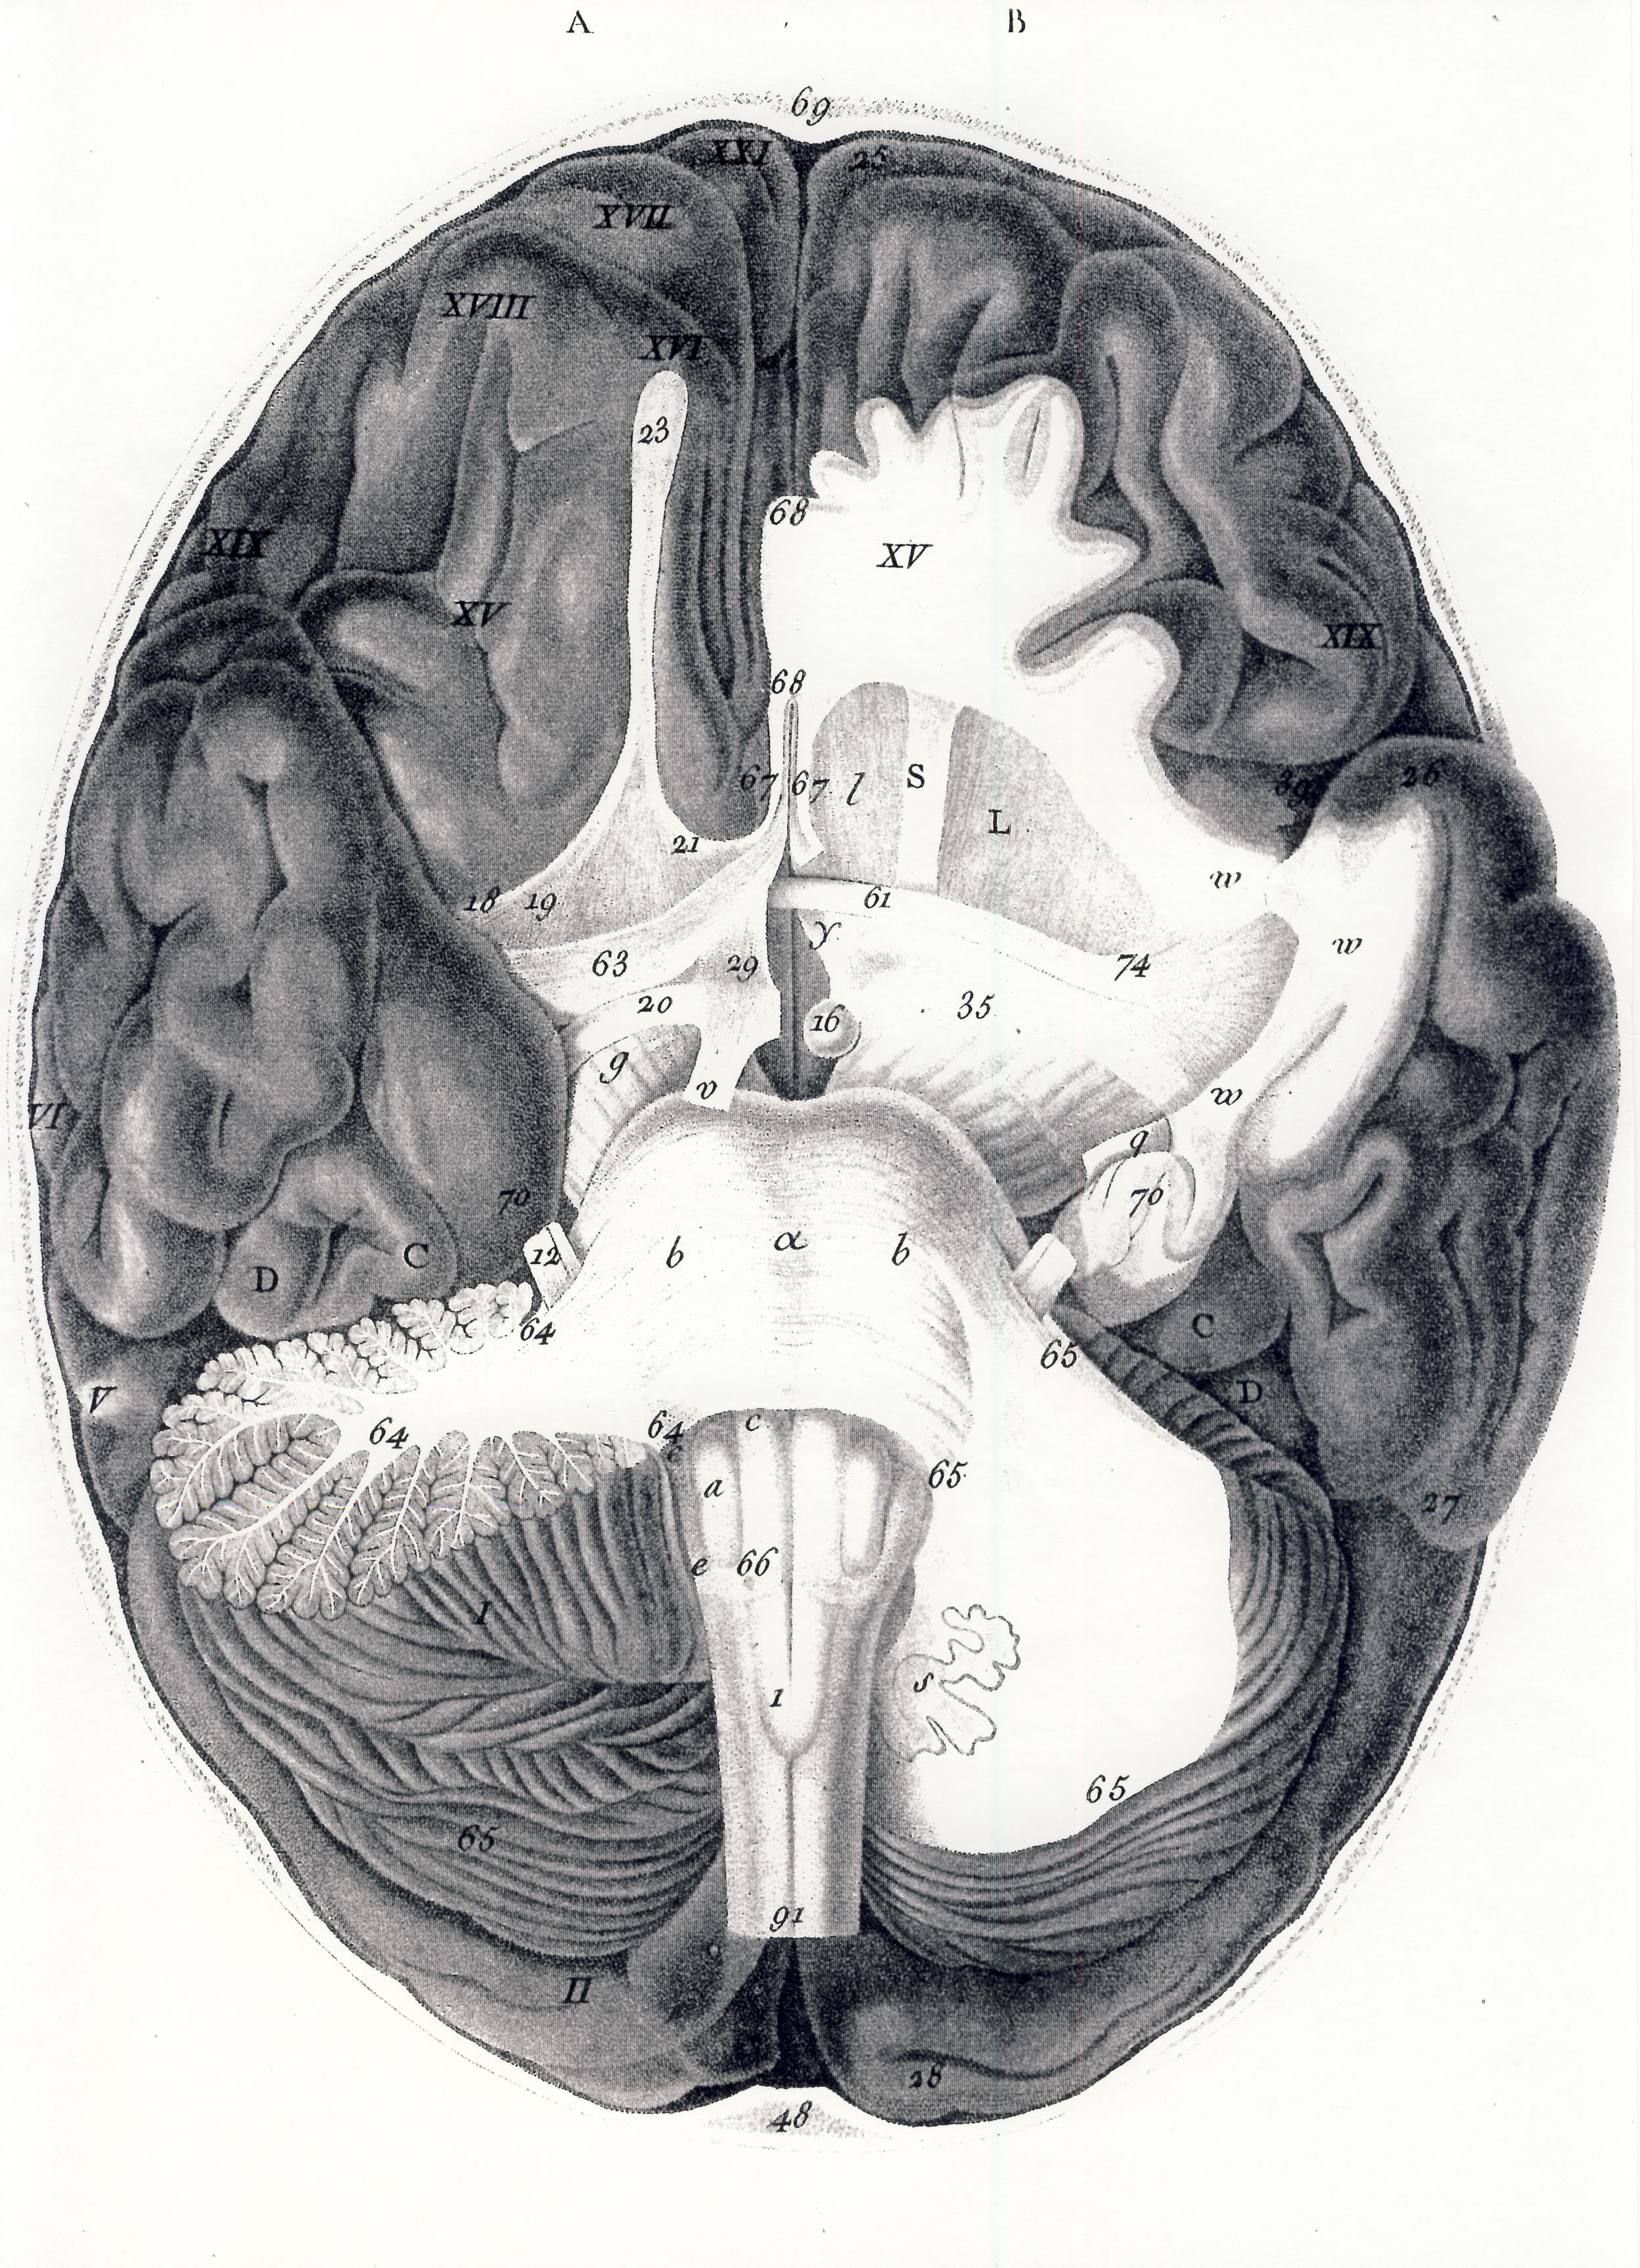

Gall, F. J. (1818). Anatomie et physiologie du système nerveux en général, et du cerveau en particulier, Avec des observations sur la possibilité de reconnoître plusieurs dispositions intellectuelles et morales de l´homme et des animaux, par la configuration de leurs têtes.

Librairie Grecque-Latine-Allemande, Vol. 3, I-XXXV u. 1-379 100 planches.